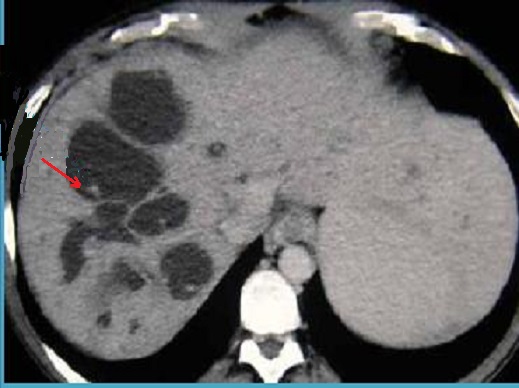

Aspect TDM de maladie Caroli est de

multiple formation lesion sacculaire a hypodense

intrahepatique et pas de rehaussement apres

injection de contrast intraveineuse .Une

branche de veine porte peut entourne par lesion

sacculaire se donne image de ''central dot sign

''intra kystique .. |

Image radiologique TDM en coupe axiale

du syndrome de Caroli avec lesion multiple en

forme kystique a hypodense des voies biliaires

intrahepatiques . |

Image de lesion kystique multiple a hypodense

situe au foie droit du maladie de Caroli . Signe de

''central dot sign '' se retrouve dans plusieure de

kyste ( fleche rouge ) . Une propiete specifique des

lesion kystique est ne rehaussement pas apres

injection de contrast intraveineuse . Image

radiologique TDM plus C+ en coupe axiale . |